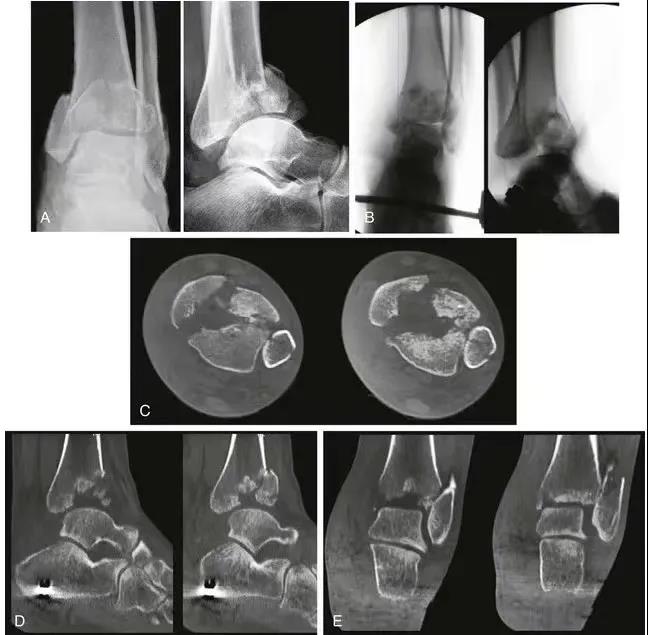

复杂pilon骨折的复位和内固定。A和B,腓骨钢板和跨关节外架的应用。注意关节面的压缩(箭头)。 C,前内侧切口。注意胫前肌腱(黑色箭头)和胫骨干骨折(白色箭头)。 D,关节面的复位。E,使用克氏针复位,然后使用螺钉固定。F应用中和钢板。G和H,术后轴和关节面的前后位X线片和侧位X线片。